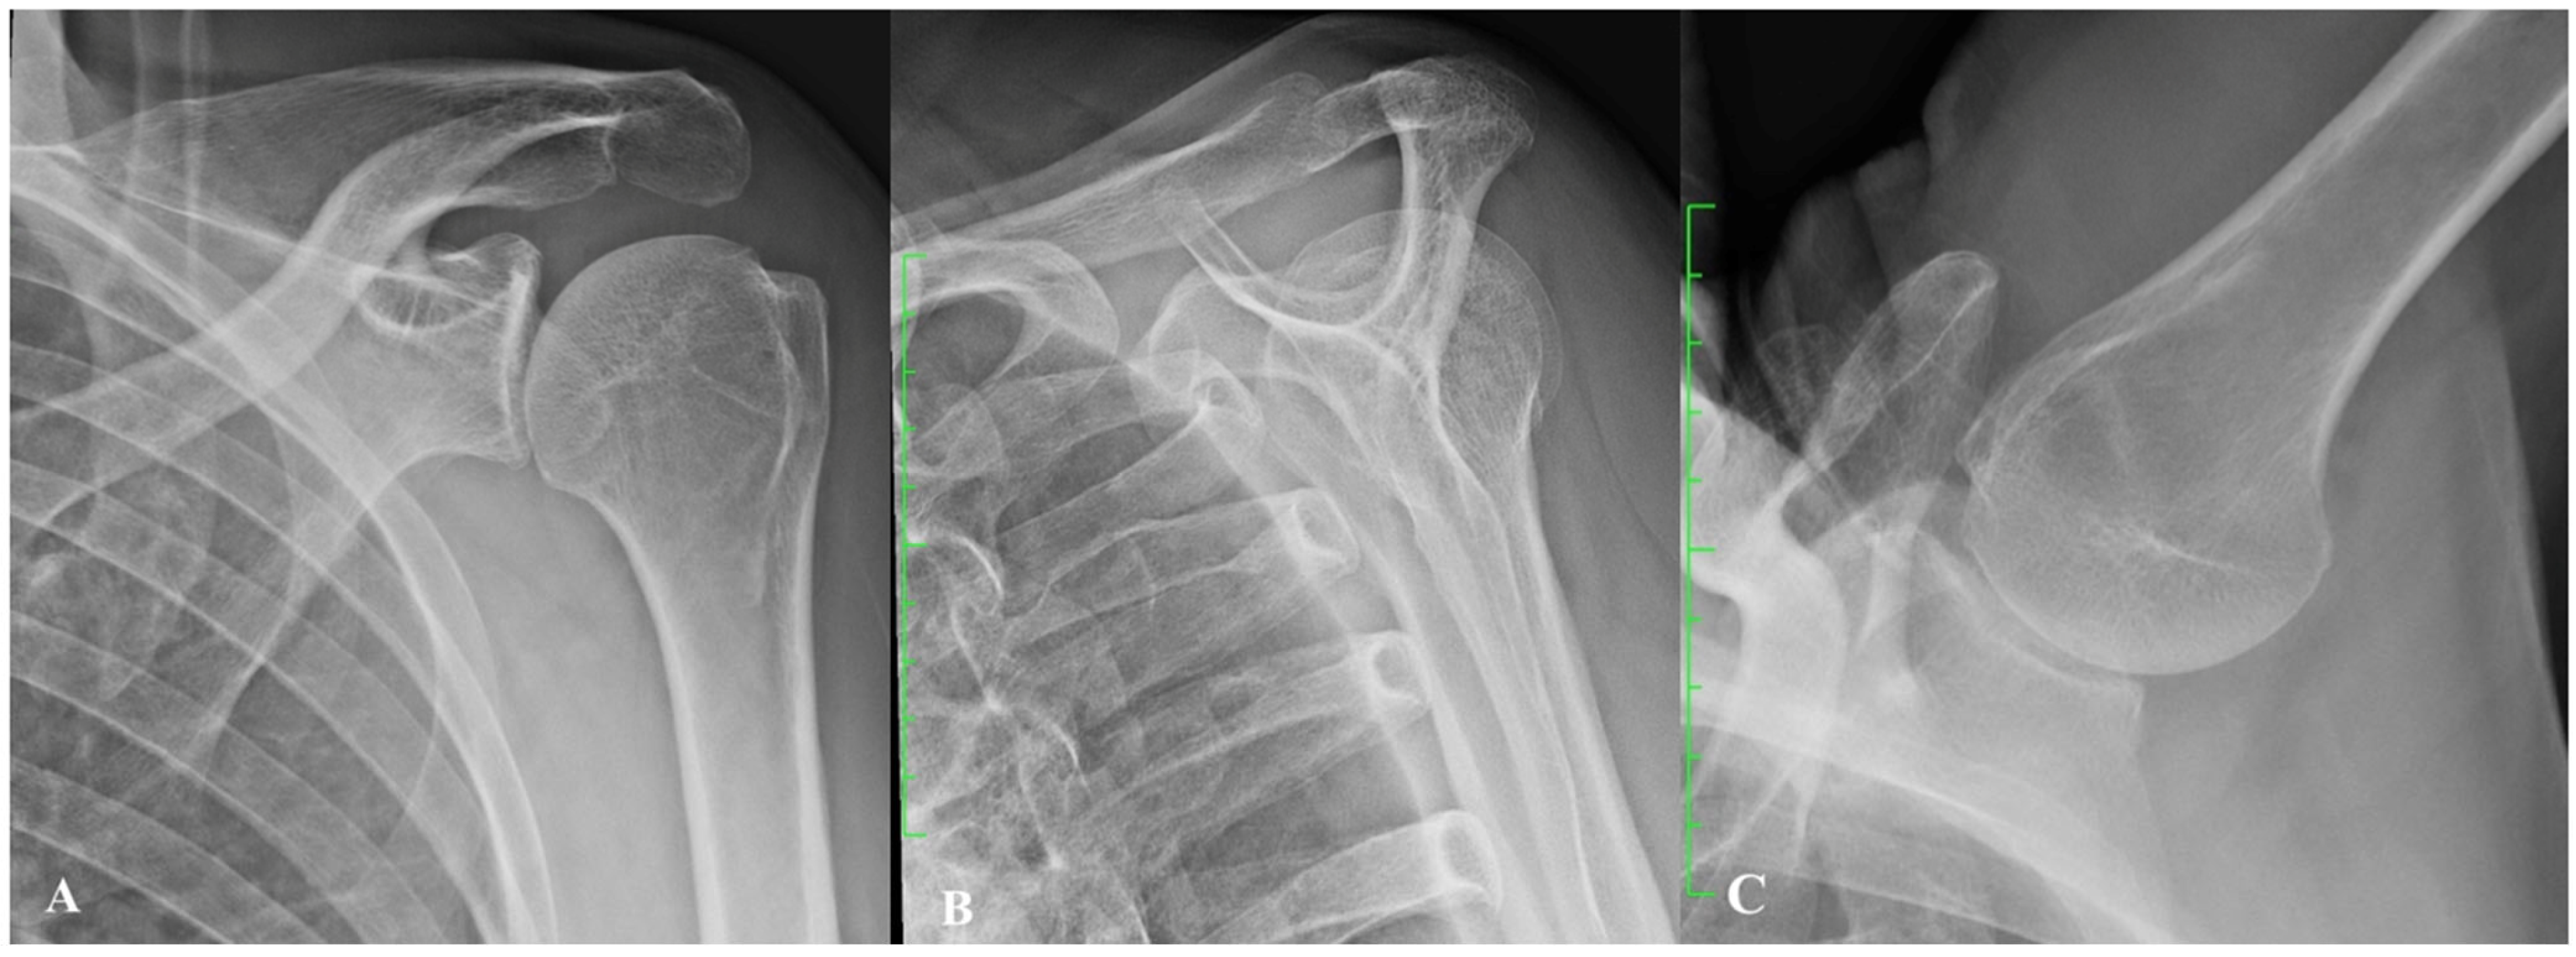

2. Gleno-Humeral Deformity in Primary Osteoarthritis and Cuff Tear Arthropathy